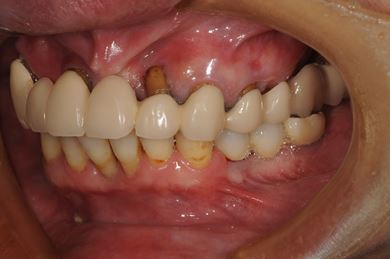

インプラントの症例写真 IMPLANT

インプラント治療+セラミック治療

| 性別/年齢 | 女性 / 59歳 | ||||||||||||||||||||||||||||||||

| 主訴 | 上の奥歯がむし歯で治したい。下の歯が少ないので、インプラントか入れ歯、できれば併用で。 | ||||||||||||||||||||||||||||||||

| 治療方針 | インプラント治療にて、機能的・審美的回復を行う。 | ||||||||||||||||||||||||||||||||

| 治療内容 | インプラント3本、ハイブリッドセラミッククラウン5本 | ||||||||||||||||||||||||||||||||

| 総治療費 | 1,116,308円 | ||||||||||||||||||||||||||||||||

| 治療期間 | 7ヶ月 |